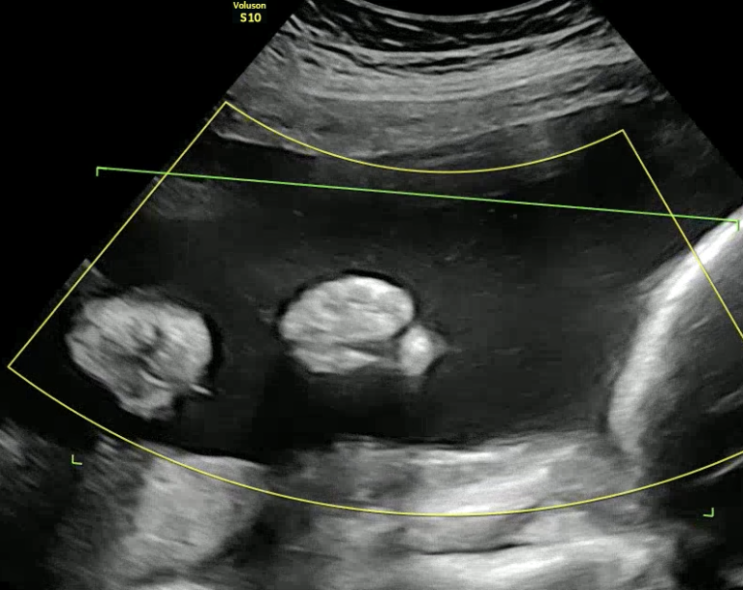

임신중일기_5. 26주차 초음파. 귀여운 얼굴 보여준 한방이! 입체초음파? 임신성당뇨 검사(너무나 지루해..)

오늘은 한나산부인과, 한나여성병원에서 한 26주! 입체초음파, 임신성당뇨 검사 이야기? 병원 도착하자...